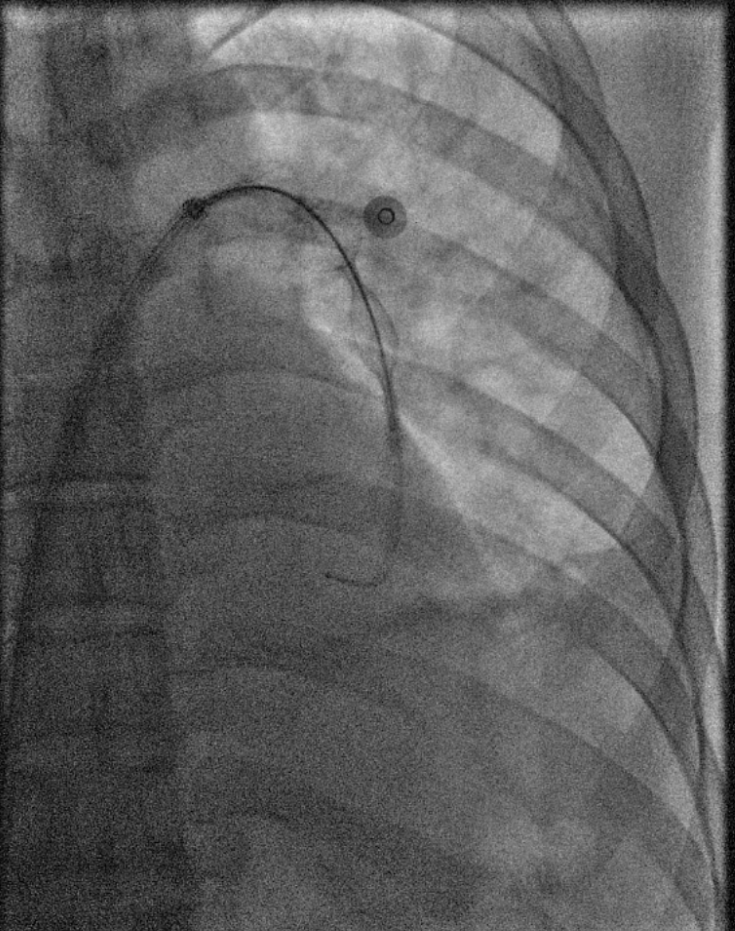

术中导管抽吸血栓、支架取栓